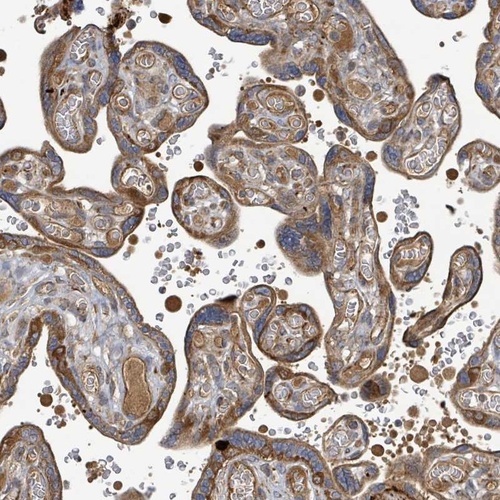

Immunohistochemical staining of human placenta shows moderate cytoplasmic positivity in trophoblastic cells.